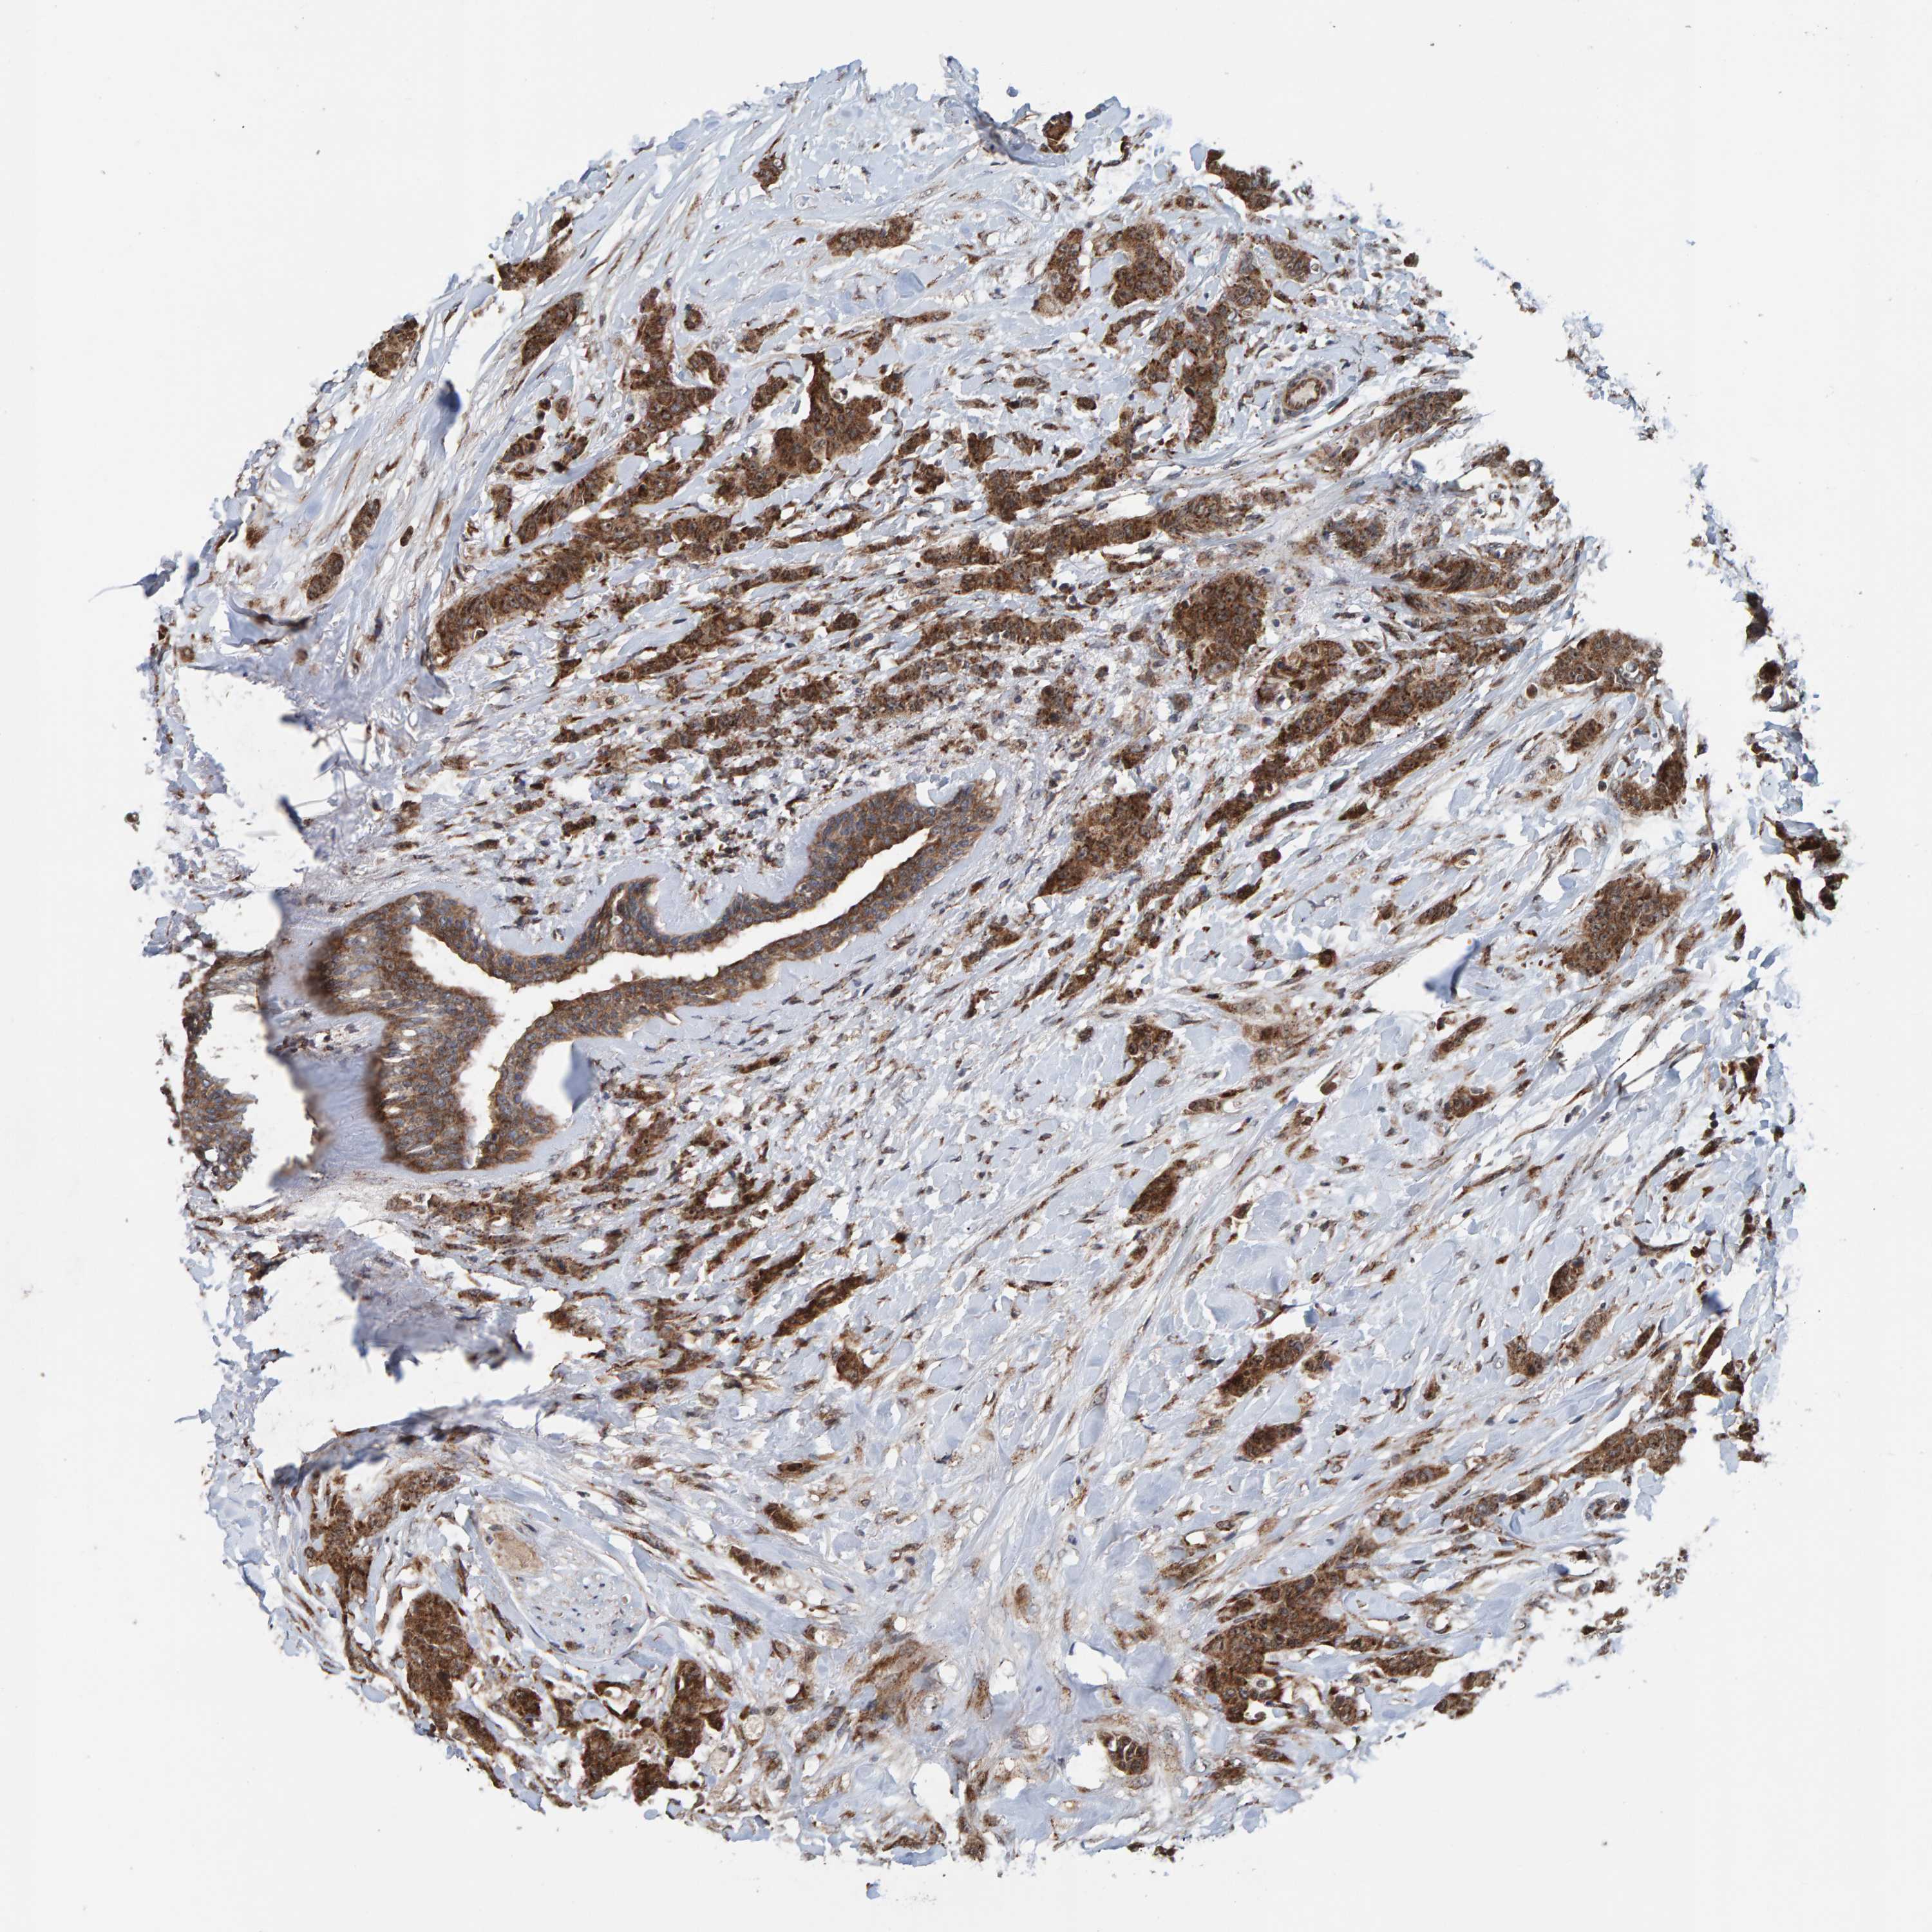

CANCER BREAST CANCER Show tissue menu

BRCA TCGA BRCA VALIDATION PROTEIN EXPRESSION